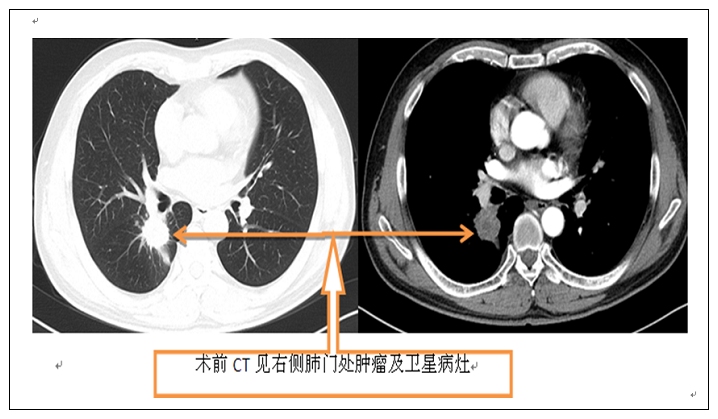

今年以来,放射科介入治疗团队顺利完成了数例肺癌的微波消融术。这是放射科继独立开展肺癌的支气管动脉灌注栓塞术、放射性粒子植入术后,进一步完善了肺癌的微创治疗手段。虽然每一位患者的病情、症状不尽相同,但术后均取得了疗效。不仅缓解了患者的不适症状,且复查胸部CT可以看出,消融后的肿瘤病灶出现坏死,局部形成空洞,病灶大小保持稳定或较前缩小,达到预期治疗效果。这一治疗技术的顺利开展,将为铜陵及其周边广大肺癌患者带来福音。